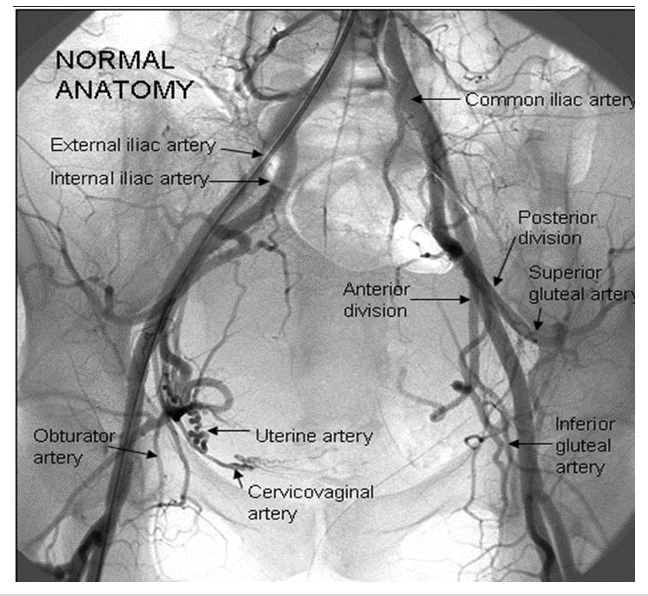

Complete the blanks & what imaging modality is this?

A

Female pelvic arteriogram

Imaging modality